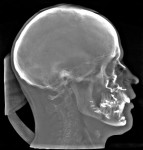

The patient is then awakened and sent to either the intensive care unit overnight or the surgical floor, depending on any preoperative comorbidities and the operative course. Hospital stay is generally 1 to 2 nights. A postoperative CBCT is taken on postoperative day 1. In the present case, the postoperative CBCT, as compared to a preoperative CBCT, demonstrated the successful results of the treatment (Figure 13 and Figure 14).